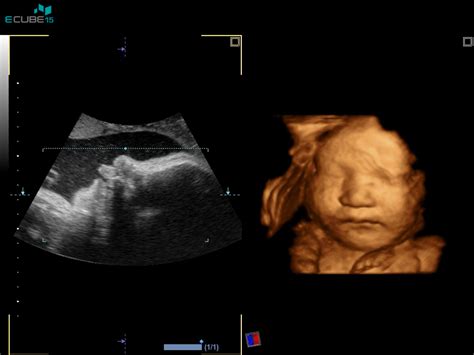

3D/4D Ultrazvok: Ta napredna tehnologija omogoča pogled na plod v treh dimenzijah, kar je še posebej zanimivo za starše, ki želijo videti obrazek svojega otroka ali opazovati njegove gibe. 3D/4D ultrazvok je pogosto na voljo med 25. in 30. tednom nosečnosti. Cene se gibljejo med 60 € in 120 €, pri čemer lahko doplačate za snemanje na USB ali CD.